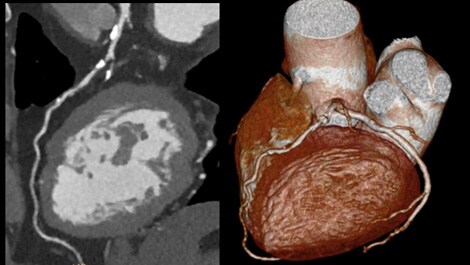

• Precise Cardiac: ZeroClick-Technologie kompensiert die Herzbewegung bei hohen Herzfrequenzen.

Philips Incisive CT Precise Suite - Beispiel Cardio